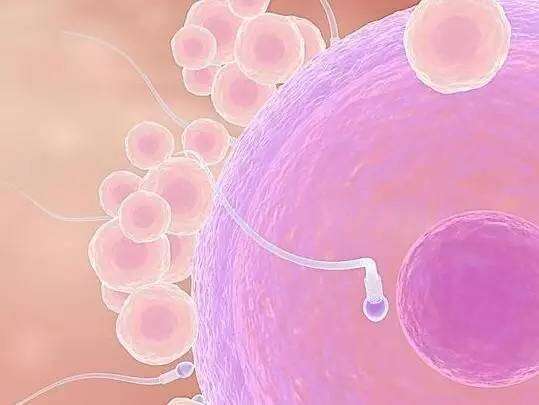

| 宫外孕病因五 | 受精卵游走

|

| 宫外孕病因六 | 受精卵游走

|